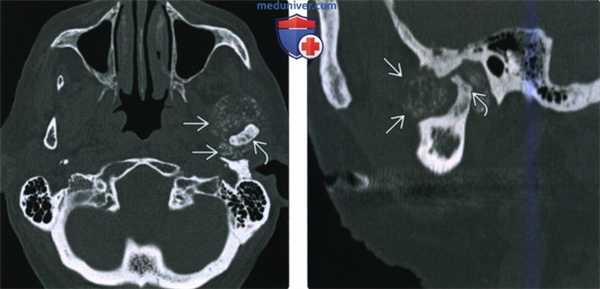

(Слева) КТ в костном окне, аксиальная проекция. Типичная хондросаркома левого височно-нижнечелюстного суаава. Мыщелок нижней челюсти склерозирован и имеет неправильную форму, внутри и вокруг сустава рассеянны множественные кальцификаты. И хотя в данном случае достаточно сложно дифференцировать заболевание от синовиального хондроматоза, в обоих случаях лечение должно быть хирургическим, а точный диагноз будет установлен после гистологического исследования.

(Справа) Реконструкция в сагиттальной плоскости, этот же пациент. Мыщелок деформирован, а часть кальцификатов находится в мягких тканях вне сустава.

(Слева) На аксиальной КТ в костном окне визуализируется типичная хондросаркома ВНЧС с множественными кальцинатами. Мыщелок нижней челюсти слева неравномерно склерозирован, в ВНЧС и вокруг него визуализируются множественные мелкие очаговые кальцинаты.

(Справа) На сагиттальной реформатированной КТ у этого же пациента определяется деформация мыщелка. Некоторые кальцинаты, вероятно, находятся в мягкотканном компоненте за пределами сустава.